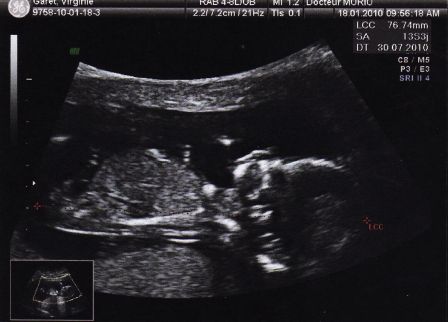

Bébé à 5 mois de grossesse

Par Virginie et Julien Garet le dimanche, mai 16 2010, 00:19